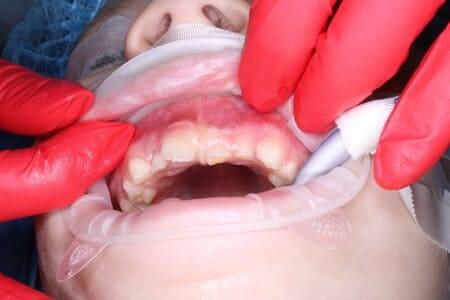

Ласкаво просимо до Центру Дитячої Стоматології Лікаря Ковнацького – місця, де турбота про посмішку вашої дитини стає безтурботною пригодою!

Детальніше...У Центрі Дитячої Стоматології лікаря Ковнацького ми віримо, що візит до стоматолога має бути для дитини не приводом для страху, а кроком до здорової та щасливої посмішки. Наша філософія базується на глибокому розумінні дитячої психології та фізіології, адже дитячі зуби потребують особливого підходу, а малюки – щирої турботи та довіри.